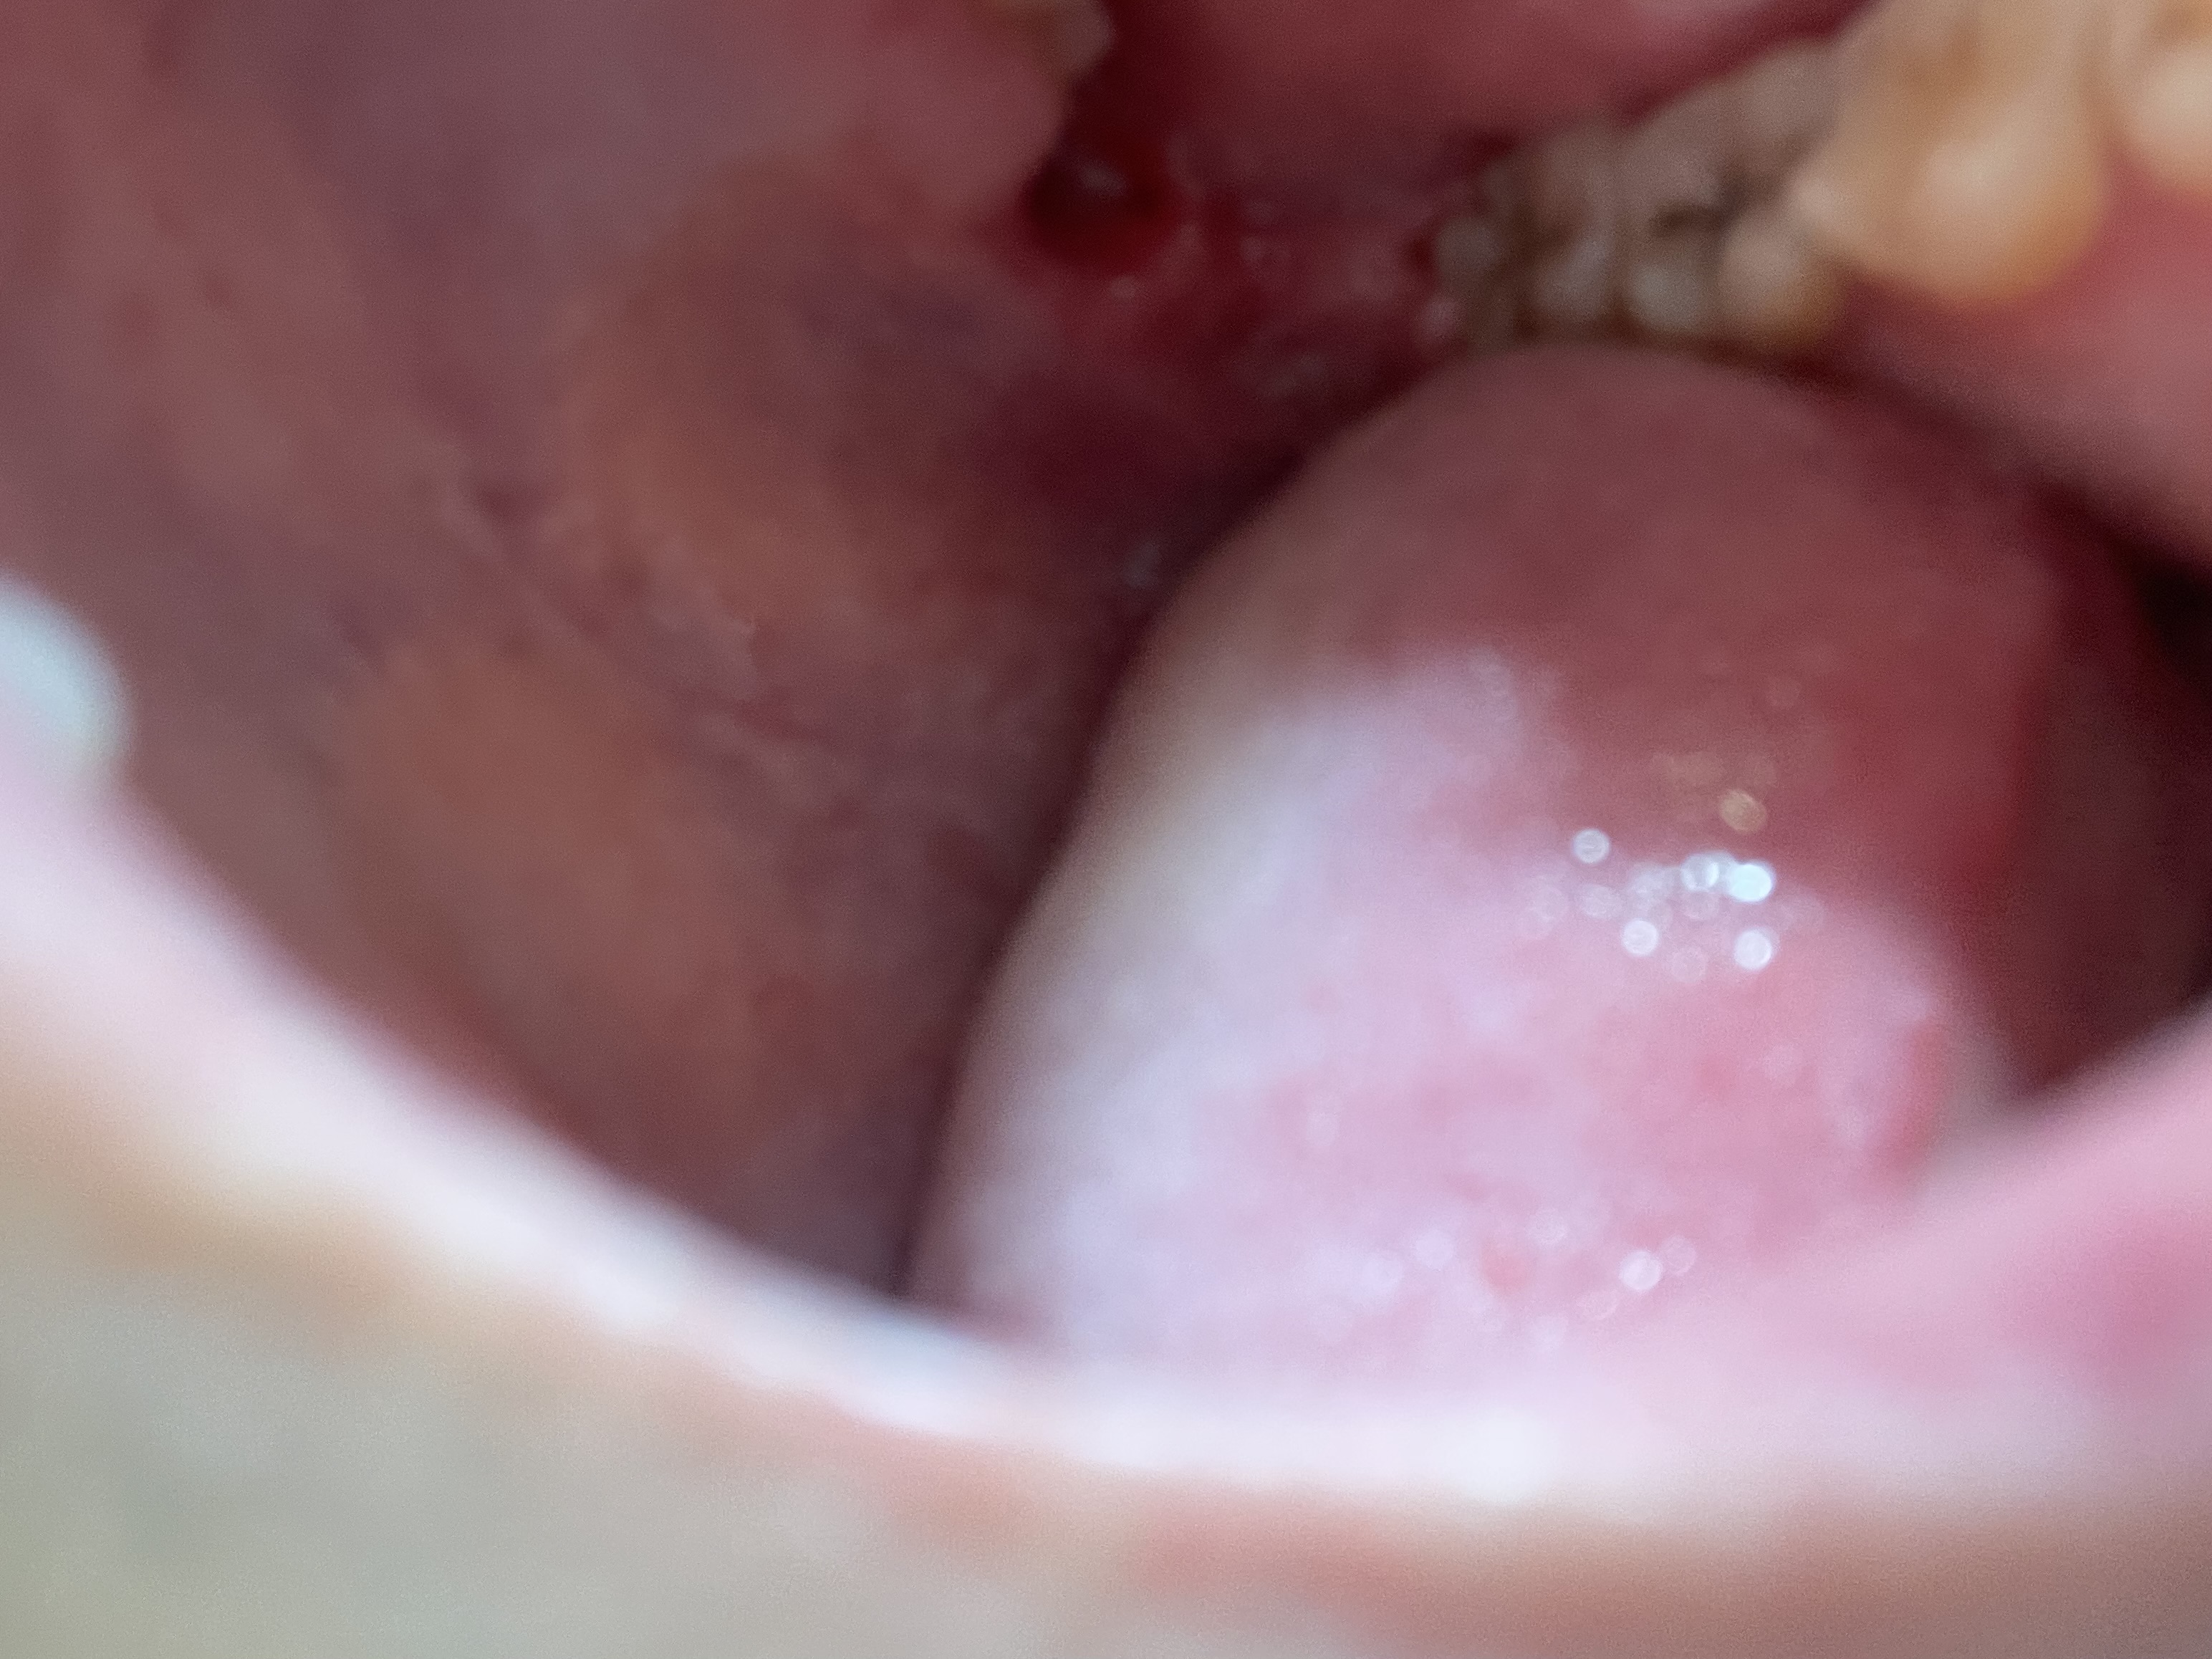

頬の粘膜に口内炎が潰れたような見た目のできものがあります。

回答数:2 -